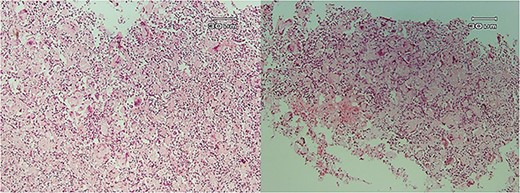

Microscopic examination showed (Figs 4–7) inflamed connective tissue composed of prominent plasma cells mixed with numerous osteoclastic multinucleated giant cells of various sizes with intracytoplasmic asteroid bodies and round Schaumann bodies, which surrounding round to amorphous eosinophilic areas composed of the spindle to stellate cells in fibromyxoid background is also evident.

Histopathologic views of the lesion (H&E staining, ×100 magnification). (A) Inflamed fibromyxoid connective tissue. (B) Area of one granulomatous pattern inflammation with multiple giant cells. (C) Numerous foreign body giant cells admixed with severe chronic.

Histopathologic views of the lesion (H&E staining, ×100 magnification). Inflamed fibromyxoid connective tissue and foreign body giant cells.